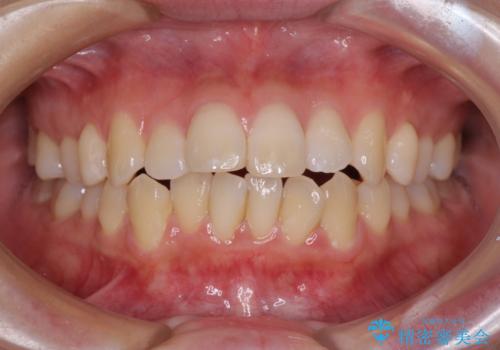

出っ歯を改善 目立たないワイヤー装置での抜歯矯正

- 口元の突出感と口の閉じにくさを気にして来院された患者様です。

上下左右第一小臼歯4本を抜歯し、ワイヤー装置にて口元を引っ込めるよう矯正治療を行うこととしました。

2年~2年半が治療期間の目安でしたが、順調に治療が進み、1年9か月で満足のいく歯列となりました。